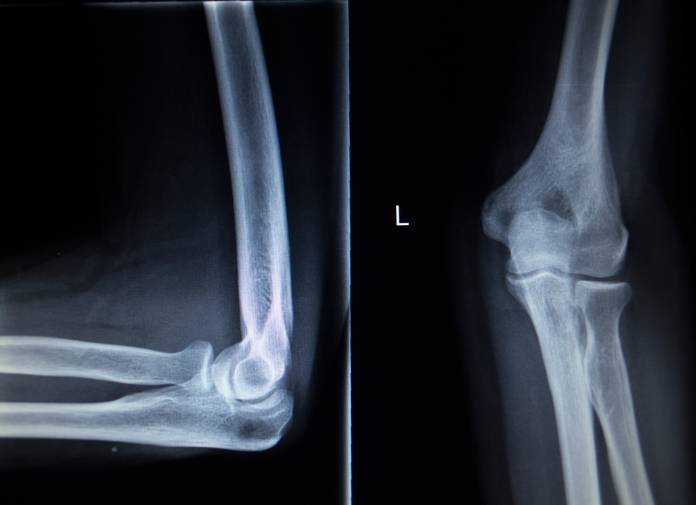

Nach der körperlichen Untersuchung folgt ein Ultraschall. Auf dem Ultraschall sind entzündete Sehen als verdickte Stränge sichtbar. Ein Ultraschallbild ist eine recht ungenaue Methode. Sie ist aber ohne jede Belastung des Patienten durchführbar. Auf einem Röntgenbild können krankhafte Verkalkungen am Beginn einer Sehne sichtbar gemacht werden. In einzelnen Fällen, wenn der Arzt sich seiner Diagnose unsicher ist, kann er ein Magnetresonanztomogramm (MRT) anfertigen lassen. Hierbei wird der Körper in dünnen Scheiben dargestellt. Der Vorteil des MRT liegt darin, dass es ohne Strahlungsbelastung durchgeführt wird und dass auf den Bildern die Muskeln und Sehnen in hoher Qualität abgebildet werden.